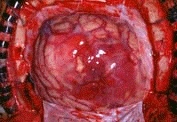

”]‚Ì•\–Ê‚ÉÔ‚¢F‚ð‚µ‚½Žîᇂª˜Io‚µ‚Ä‚¢‚é‚Ì‚ª

ŠÏŽ@‚³‚ê‚Ü‚·B